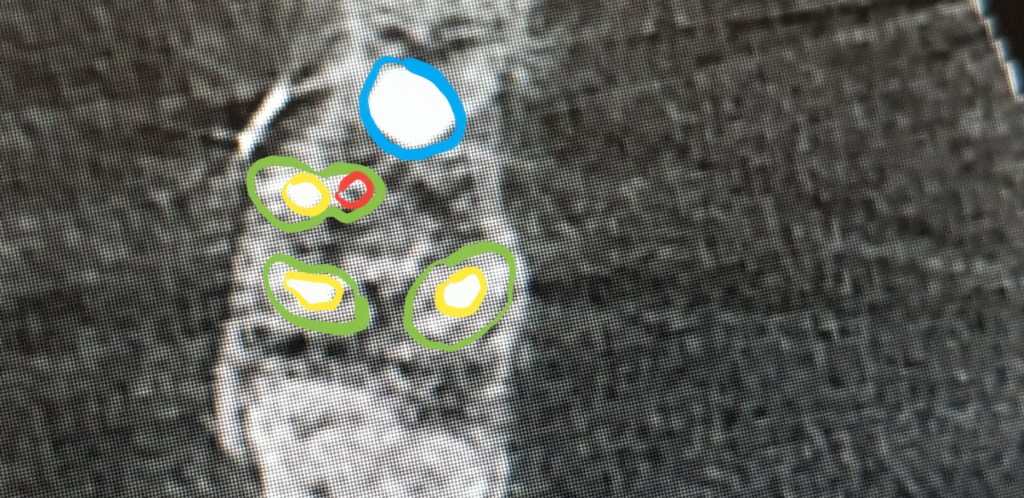

A CT felvétel kiértékelése feloldja az ellentmondásokat, ugyanis a 3D röntgenen eddig nem látott területek is láthatóvá válnak. A horizontális keresztmetszeti képen ugyanis előbukkan egy apró kezeletlen gyökércsatorna (pirossal jelölve) és 3D-ban a gyökércsúcson is láthatóvá válik a gyulladás okozta csontdefektus.

Az felső első nagyörlők 4. csatornája kis méretük és rejtettségük miatt gyökérkezeléskor gyakran nem kerülnek ellátásra.

Néhány héttel a nagyörlő rejtett 4. csatornájának célzott megkeresése és kezelése után eltűnik a panaszt okozó váladékozó duzzanat. A fog csapot, koronát kap majd és jó eséllyel szájban töltheti a következő évtizedet is.

Panaszt okozó korábban gyökérkezelt fogaknál tehát mindig fel kell vetni esetlegesen meg nem talált és/vagy teljesen ki nem tisztított gyökércsatornák jelenlétét, melyek figyelmen kívül hagyása a fog elvesztését okozhatják.

A CT felvétel (3D röntgen) készítése bizonyos esetekben indokolt lehet és nagy segítséget jelenthet a probléma okának felderítésében.